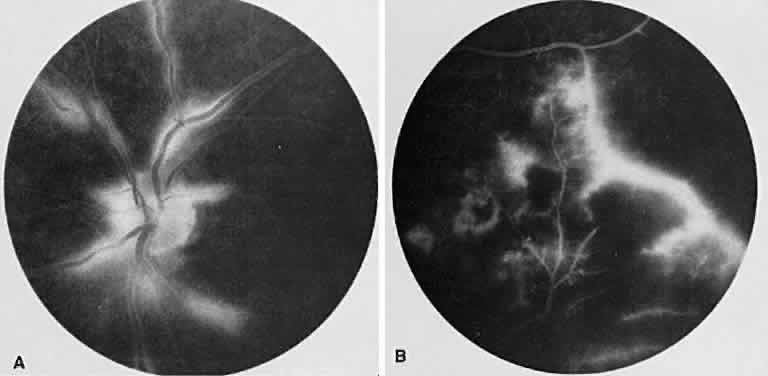

BEHÇET'S DISEASE

Behçet's disease is a systemic occlusive vasculitis that presents predominately in young middle Eastern and Japanese men. The classic features include acute hypopyon, iritis, aphthous stomatitis, and genital ulceration. Skin lesions and strokes also occur frequently. There often is an acute recurrent bilateral panuveitis. Ocular findings include retinal vasculitis (Fig. 6A) with an occlusive arteritis, vitritis, macular edema, ischemic retinitis, ischemic optic neuropathy, peripheral neovascularization, and occasionally SRNV.

Fig. 6. Behçet's disease. A. Fundus photograph showing vasculitis of the superotemporal vascular arcade. Intraretinal hemorrhages also are seen. B. Fluorescein staining of the vessel wall and adjacent areas of blocked fluorescence corresponding to the intraretinal hemorrhage.

On fluorescein angiography (see Fig. 6B), during the active phases of the disease, capillary dropout and dilated retinal capillaries are seen. Dilated retinal capillaries (particularly peripapillary capillaries) leak dye and cause retinal and disc staining.19 Cystoid macular edema,19 SRNV, and disciform scars often are seen.20 Leakage of peripheral capillaries can be seen in patients with normal-appearing fundi.21

ICG angiography shows hyperfluorescent spots from the early to late phases and hypofluorescent plaques, both of which are not evident on FA. Staining of choroidal vessel walls and leakage of ICG from the choroidal vessels also have been described.22–24